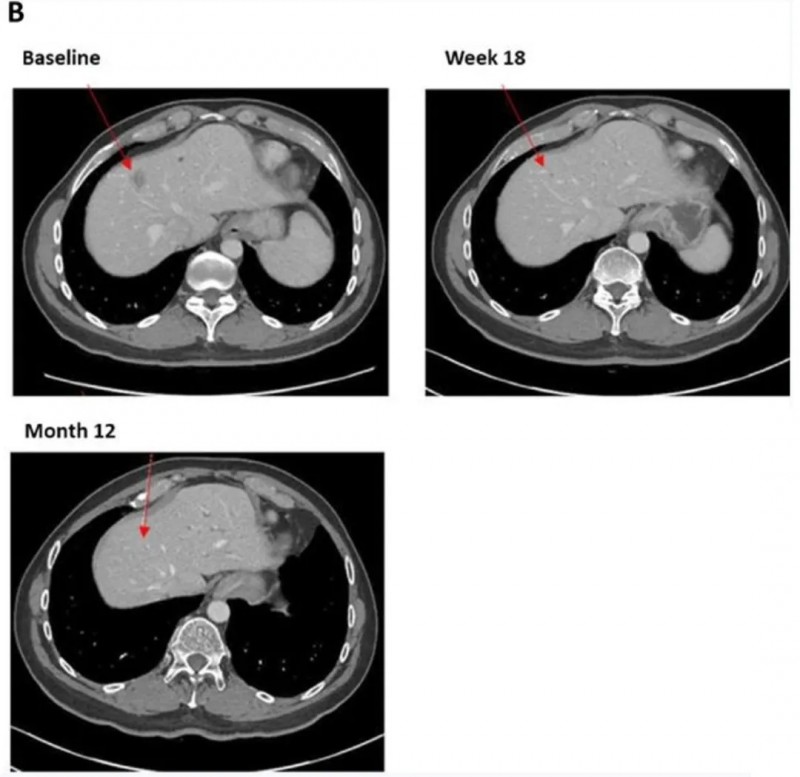

1、疾病控制率(DCR):整体DCR为62.5%(95%CI:35.4%-84.8%)。其中10例患者至少一次评估达到SD;12周时,5例患者(31.3%)达到SD,涵盖3例CRC、1例PDAC、1例OVCA。其中1例PDAC患者的SD持续17个月,虽未缩小原发灶,但部分转移灶缩小或消失(详见下图)。

▲图源“BMJ”,,版权归原作者所有,如无意中侵犯了知识产权,请联系我们删除